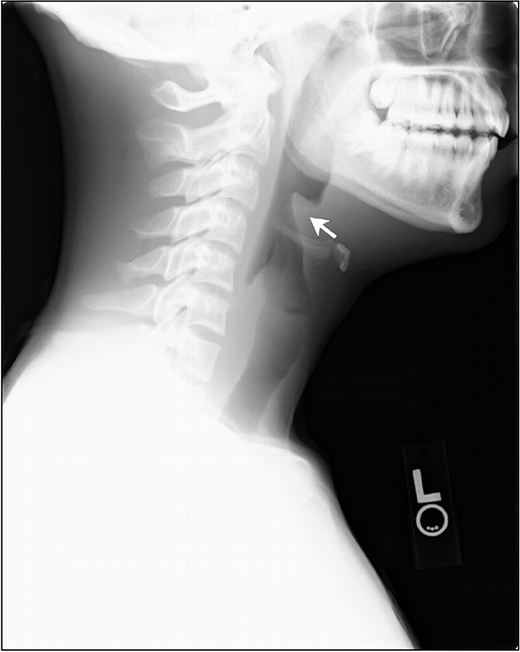

破伤风(锁颚)

- 颞下颌关节 (TMJ) 脱位

- 椎体压缩性骨折

- 长骨骨折

诊断:基于病史和临床发现的诊断;

- 新生儿 – 在出生后的前两天内吸吮和哭闹正常的婴儿,在出生后 3 至 28 天出现吸吮和哭闹丧失,然后出现僵硬和痉挛

- 非新生儿破伤风诊断需要牙关紧闭、肉面跳动,以及伤口或损伤史。

- 抹刀试验阳性:用软器械抚摸咽后壁导致反射性下颌痉挛 – 诊断临床破伤风的灵敏度为 94%,特异性为 100%